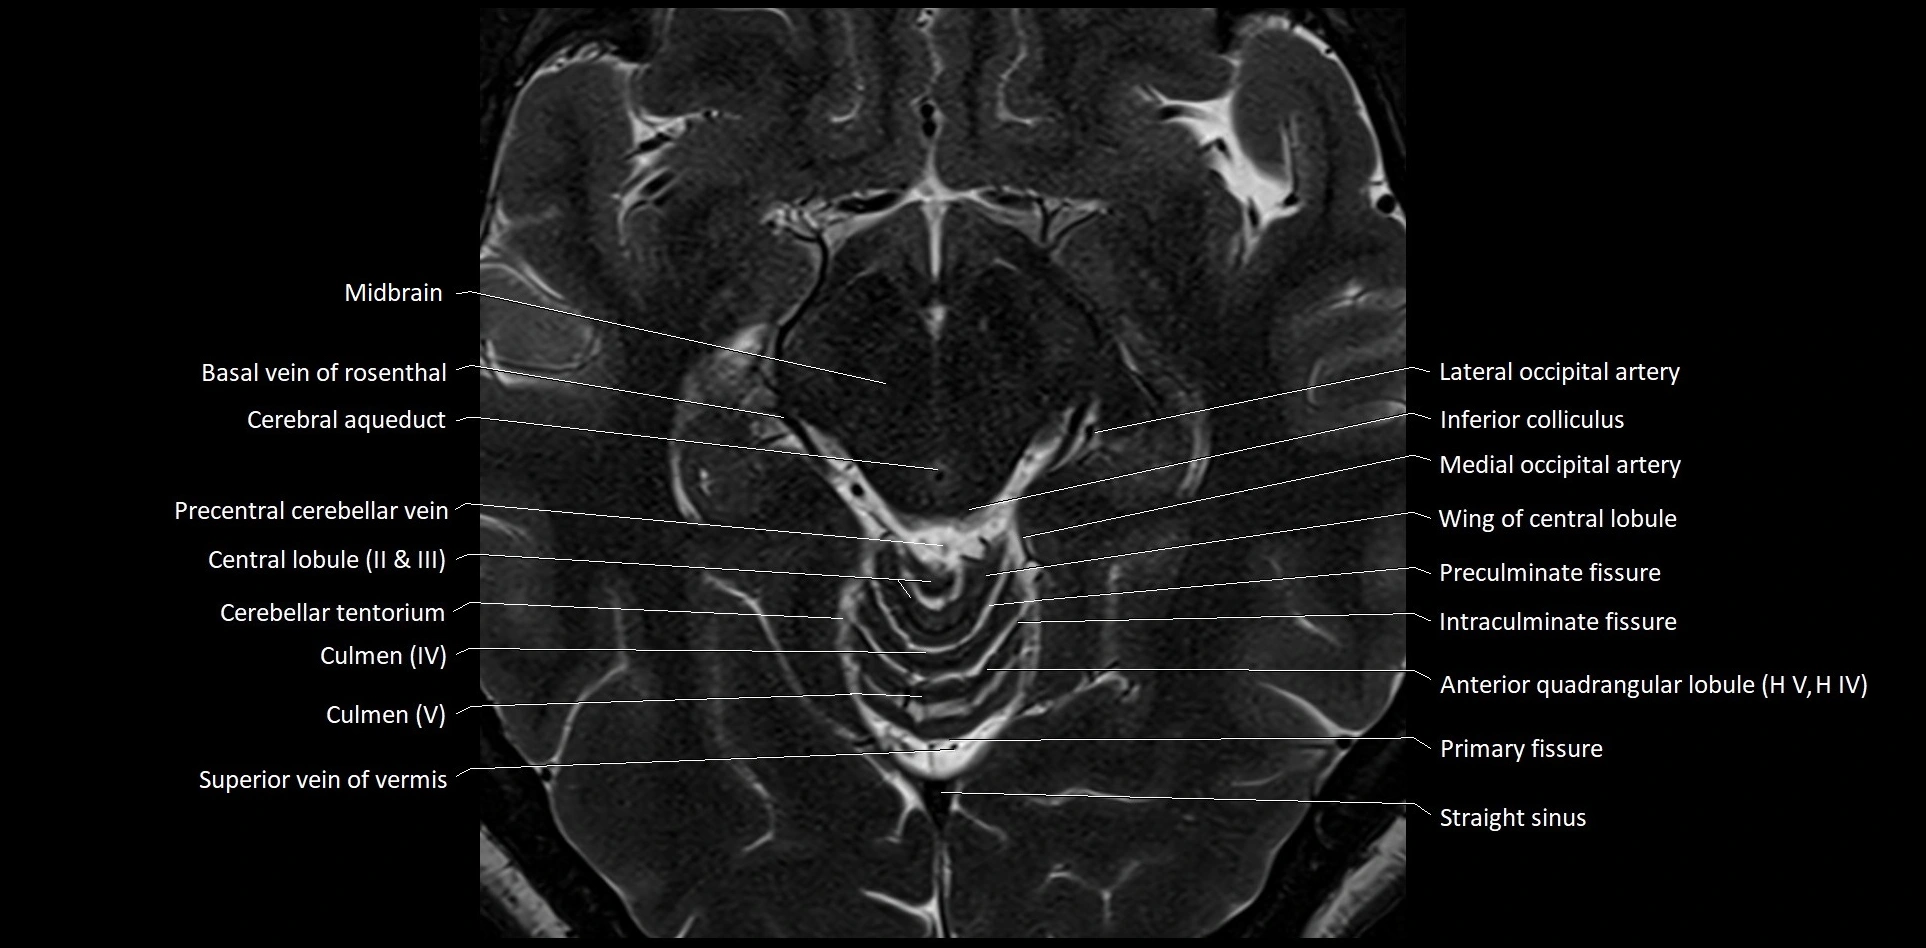

- Cerebellar tentorium

- Culmen

- Culmen (IV, V) of Cerebellum

- Lateral occipital artery

- Medial occipital artery

- Precentral cerebellar vein

- Preculminate fissure

- Straight sinus

- Superior vein of vermis